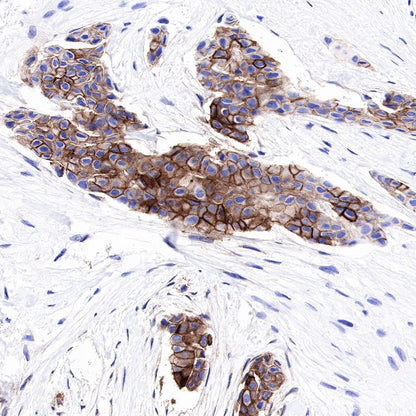

IHC shows positive staining in paraffin-embedded human lung adenocarcinoma. Anti-CEA(CD66e) antibody was used at 1/1000 dilution, followed by a Goat Anti-Rabbit IgG H&L (HRP) ready to use. Counterstained with hematoxylin. Heat mediated antigen retrieval with Tris/EDTA buffer pH9.0 was performed before commencing with IHC staining protocol.